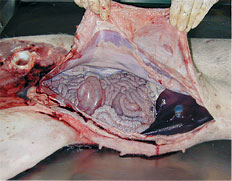

Autopsie des animaux atteints

Bien que la symptomatologie de la MAP et ses lésions macroscopiques varient, certaines découvertes d’autopsie renforcent la suspicion, voire facilitent le diagnostic de la maladie. En fait, les découvertes macroscopiques les plus représentatives de la MAP, en plus de l’amaigrissement, sont :

Ouverture de la cavité abdominale lors d'une autopsie.